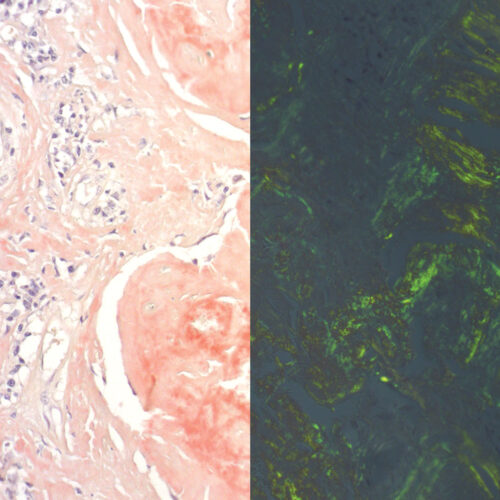

Congo Red Highman kit

Three-reagent kit for staining amyloids, characteristic for use of alkaline solution as differentiation medium in order to avoid undesirable non-specific coloration of cellular substances. Amyloid deposits display green coloration under polarized light.

Congo Red Puchtler kit

Three-reagent kit for staining amyloids, characteristic by its high ionic strength and pH enhancing the specificity of Congo Red dye binding to amyloid clusters. This method developed by Puchtler remains the gold standard for amyloids in tissue sections. Amyloid clusters have the property of double refraction that enables green coloration under polarized light.